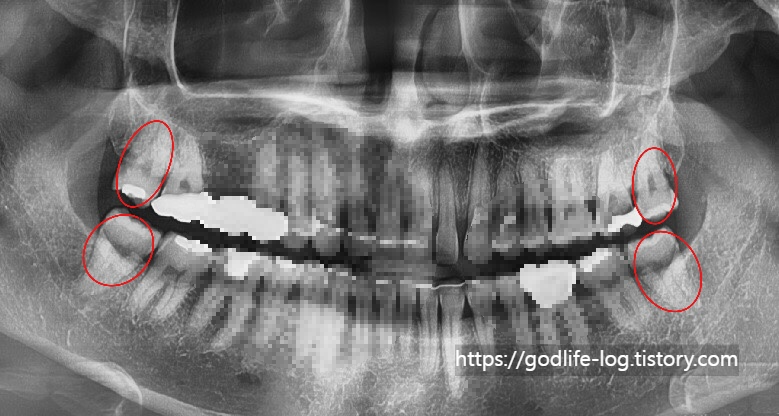

위 사진처럼 오른쪽, 왼쪽, 위, 아래 사랑니 4개 모두 일반적인 어금니와 같은 모습으로 똑바로 맹출 되어있는 경우엔 관리만 잘 된다면 크게 주변치아에 문제를 일으키지는 않습니다.